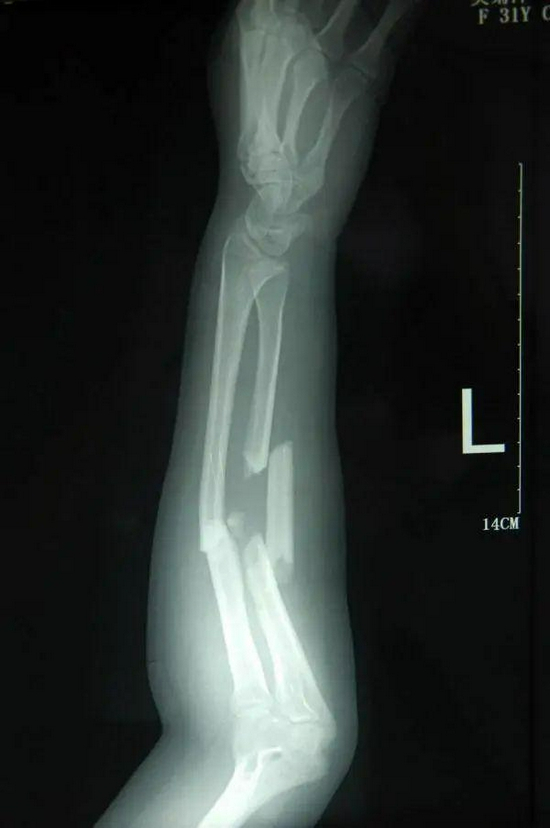

床头的信息卡上,清晰地写着一行小字:“吴菊萍,1980年出生,左尺桡骨多段粉碎性骨折。”

左尺桡骨多段粉碎性骨折,吴菊萍缠满绷带的左臂,在接住妞妞的瞬间,究竟要承受多大的冲击?

有位叫“天青”的网友曾做过详细推算:

一个2岁的孩子,我们暂定她是30斤。1层楼,我们大概算3米高,孩子从10层楼掉落,也就是掉落了9层楼,高度是27米,吴女士接住孩子的时候应该离地面大概1.5米左右,那么小女孩儿掉落的高度大概是25.5米。根据物理公式V的平方=2gs,孩子砸到吴女士手臂上时的瞬间速度就约等于22.36米每秒。

再假定,吴女士的手臂与孩子的接触时间是1秒,那么根据公式FT=MV小女孩儿接触到吴女士手臂时的那一秒,吴女士用手接住了一个335.4公斤的物体。

难以想象,吴菊萍在接住妞妞那一刹,承受的竟是335公斤的重量!而常人手臂能承受的力量不过45公斤。

事发后吴菊萍的X光片显示,她左手臂的尺桡骨断成了三截。有的碎骨甚至直接戳出皮肤,裸露出来。

连见惯了伤病的骨科医生都深感诧异:“她伤得很重,手臂受到了巨大撞击后产生爆裂伤,一般只有在车祸或机器挤压伤中才遇得到。”